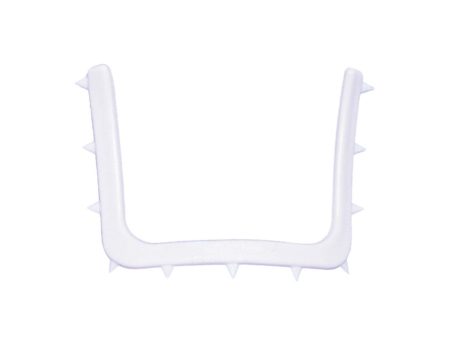

Flows through 27-gauge x 25mm endodontic irrigation needles with 2-side-vents for controlled placement and uniform coating of canal walls, and with closed end to prevent overfills.

- Easy flow formula – will not clog 27-gauge needles

TE20N – TempCanal™ Enhanced endodontic irrigation needles, (27-gauge x 1”, 2-side-vent) Pkg. of 20

TE50N – TempCanal™ Enhanced endodontic irrigation needles, (27-gauge x 1”, 2-side-vent) Pkg. of 50

TE100N – TempCanal™ Enhanced endodontic irrigation needles, (27-gauge x 1”, 2-side-vent) Pkg. of 100